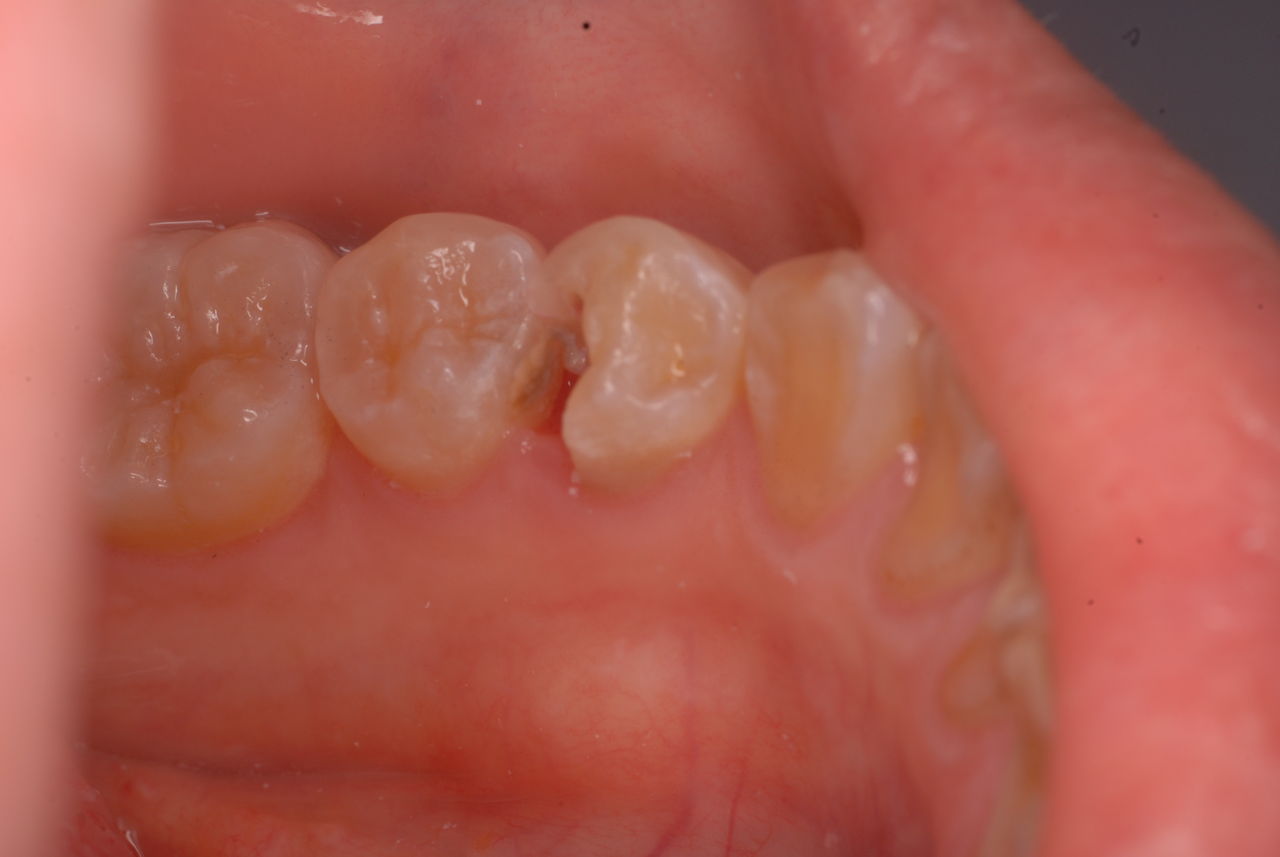

早く症状をなくすことです。被せるとか詰めることは、病気の治癒には関係ありません。

隣の歯との間をプラスチックで閉鎖し、唾液の侵入を防ぎました。でもまだ虫歯は残っています。

鎮静セメントを詰めて終了しました。後は神経の傷が治癒するのを待ちます。半年以上はかかります。